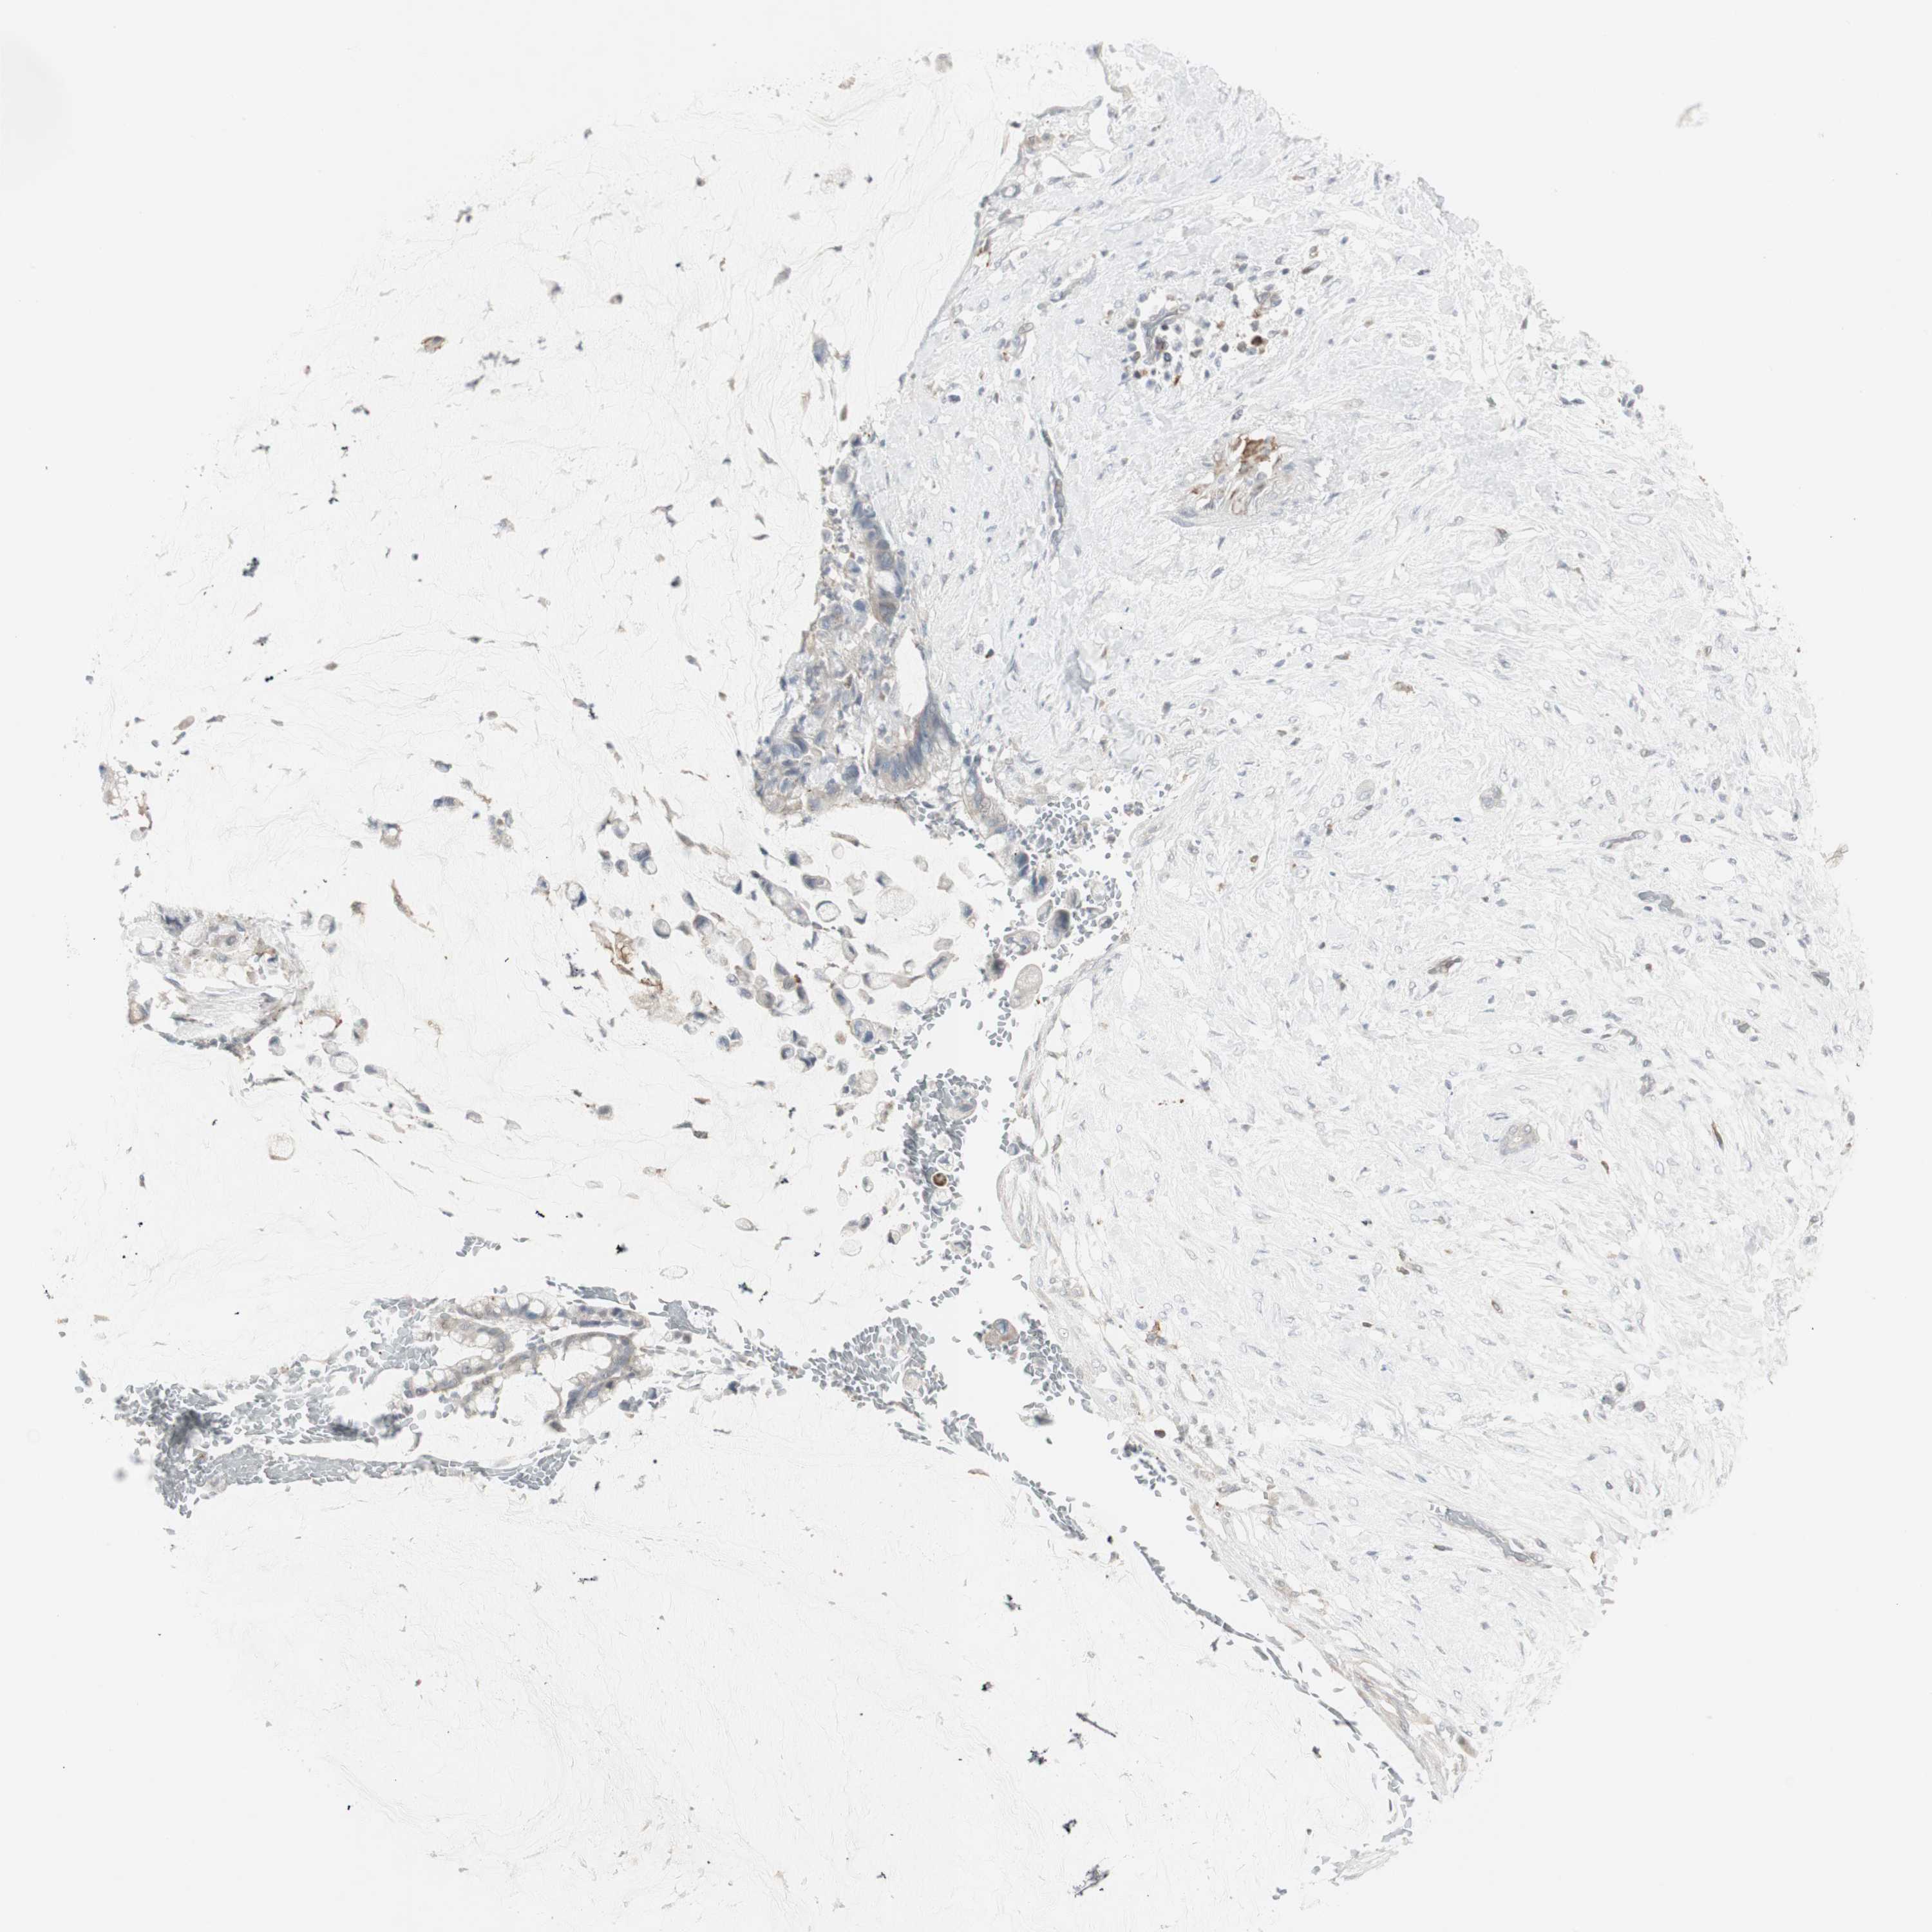

PANCREATIC CANCER - Protein expressioni

A mouse-over function shows sample information and annotation data. Click on an image to view it in a full screen mode. Samples can be filtered based on level of antibody staining by selecting one or several of the following categories: high, medium, low and not detected. The assay and annotation is described here.

Note that samples used for immunohistochemistry by the Human Protein Atlas do not correspond to samples in the TCGA dataset.

Antibody stainingi

Antibody staining in the annotated cell types in the current human tissue is reported as not detected, low, medium, or high, based on conventional immunohistochemistry profiling in selected tissues. This score is based on the combination of the staining intensity and fraction of stained cells.

Each image is clickable and will lead to virtual microscopy that enables deeper exploration of all samples and also displays staining intensity scores, fraction scores and subcellular localization as well as patient and tissue information for each sample.

Antibody HPA008476

Staining

High

Medium

Low

Not detected

Intensity

Strong

Moderate

Weak

Negative

Quantity

>75%

75%-25%

<25%

None

Location

Nuclear

Cytoplasmic/membranous

Cytoplasmic/membranous,nuclear

Adenocarcinoma, NOS